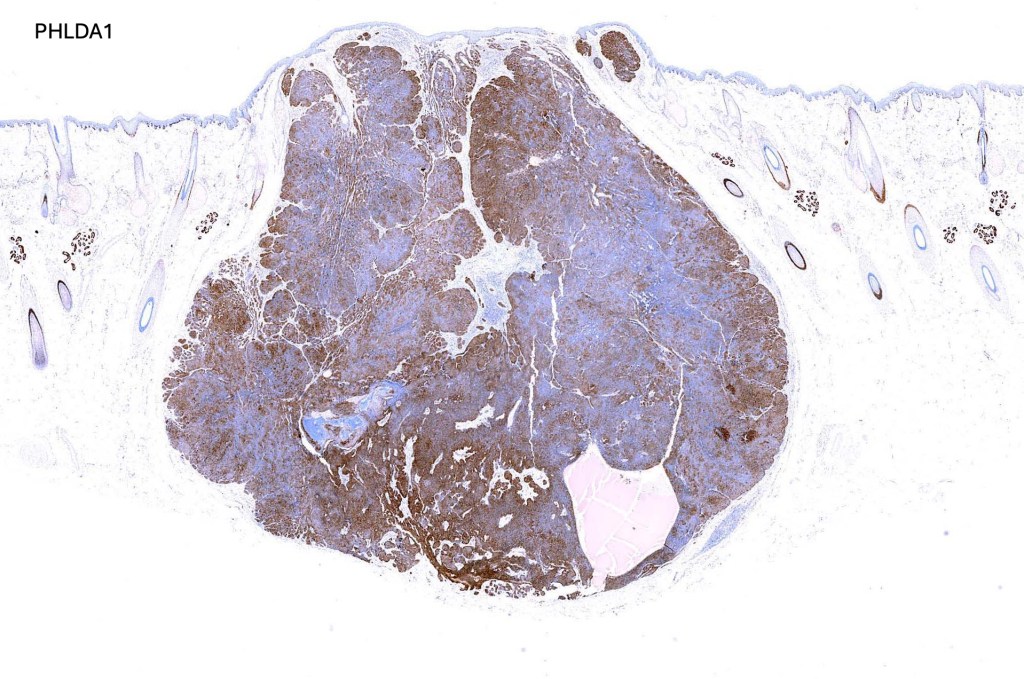

.Immunohistochemistry is included under differential diagnosis

Trichoblastoma can be distinguished from BCC by the absence of retraction artifact and stromal mucin deposition. BCC does not show papillary mesenchymal bodies. Immunohistochemical differences are shown in the table below.